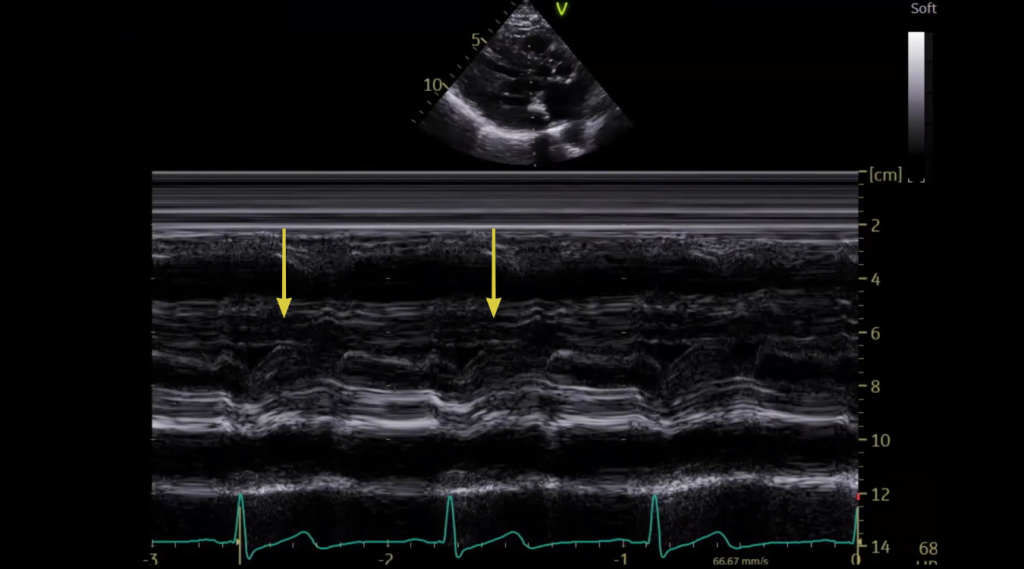

SAM on Mitral Valve M-Mode

- Place your M-mode cursor through the mitral valve tips in the parasternal long-axis (PLAX) view

- Focus specifically on systole and look for anterior motion of the mitral valve toward the septum

To consistently identify SAM utilize M-mode both on the mitral valve and on the aortic valve:

It’s true that many labs no longer rely heavily on M-mode, it can be especially helpful here.